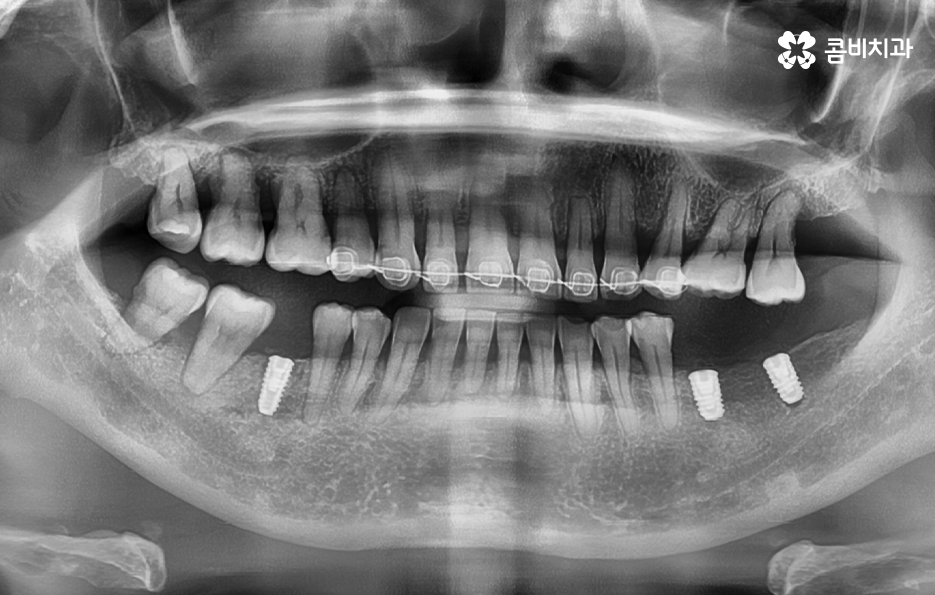

오늘 보시는 포스팅에서의 치료 과정도 어금니에 임플란트가 필요한 상태에서 윗니를 보시면 윗니가 다소 벌어진 것을 확인할 수 있는데요. 교정 하면 보통 전체교정을 떠올리게 되긴 하지만 경우에 따라서는 치열이 전체적으로 가지런한 편인데 앞니가 살짝 벌어진 경우나 어금니만 다소 벌어진 경우도 있을 거예요

이러한 경우에는 부분교정을 통해서 다소 개선이 필요한 치열을 가지런하게 만들고 가지런해진 치열과 교합 상태에 적합한 임플란트 치료 계획을 세워서 치아의 심미성과 기능적인 부분, 얼굴과의 조화를 종합적으로 고려하여 좋은 결과를 얻을 수 있어요

오늘 포스팅에서 소개드린 케이스의 경우 임플란트 치료 전에 치아교정을 통해 치료 계획을 세운 경우라면 이미 임플란트를 한 상태에서 교정에 대한 고민을 하는 분들도 있을 거예요

임플란트를 이미 한 상태에서 교정을 계획하는 경우에 대해 설명드리면 일반적으로 치열 위주로만 가지런하게 만들기 위한 치아교정은 임플란트가 크게 방해되지 않는 경우가 대부분이며 이미 치열이 삐뚠 상태에서 임플란트를 하셨던 경우에도 큰 문제가 아닌 경우가 더 많이 있는데요

임플란트를 제외한 자연치아를 우선적으로 치아교정을 하고 임플란트를 한 부위의 보철물은 새롭게 제작하거나 약간의 보철물 조정을 통해서 치료가 가능할 수 있어요